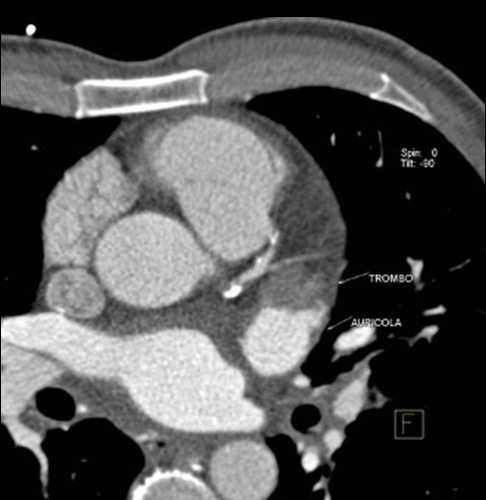

However, CCTA offers superior spatial resolution, high-quality multiplanar and 3D characterization of the LAA anatomy and accurate sizing [33]. Pre-procedural cardiac CCTA can accurately describe LA size, exclude LA thrombi and determine the anatomic feasibility of LAA occlusion procedure [34], other than better provide the ideal device size. Furthermore, utilization of CCTA 3D data may be helpful in avoiding procedure failing and complications (Fig. 2).

Fig. 2.Pre-procedural cardiac CCTA can accurately describe LA size, exclude LA thrombi and determine the anatomic feasibility of LAA occlusion procedure.